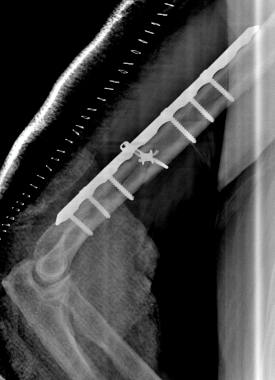

Anatomic surgical repair with plates, screws, and cable